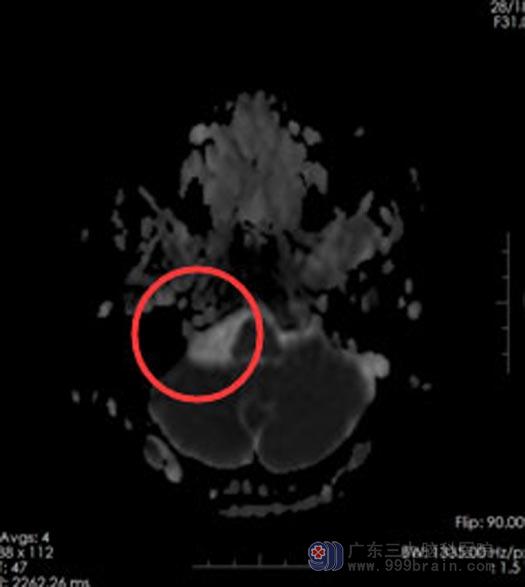

一次和邻居闲聊起这事,邻居说:人老了突然站起来容易出现低血压头晕,自己的一位朋友就是这样,建议去医院测一下血压。在医院,发现袁阿姨血压没有问题,医生建议头颅MR检查,结果提示:右侧小脑延髓池占位,考虑表皮样囊肿。

▲手术前